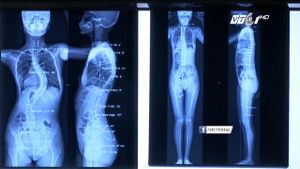

Đau cổ vai gáy dai dẳng, nam nhân viên văn phòng 26 tuổi đi khám thì bất ngờ phát hiện cột sống bị mất đường cong sinh lý, thẳng như cây gậy.